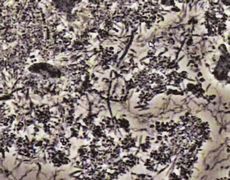

口の中で生きている細菌が歯周病を引き起こします。歯石の中に生きている細菌が酸を放出し、その酸が歯を支えている骨を溶かします。

←(顕微鏡で見た口腔細菌)